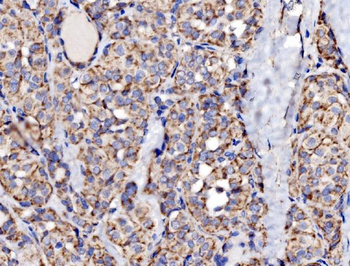

100 μl, 50 μl, 200 μl - HSC70 Mouse Monoclonal Antibody [orb704174]Featured

IF, IHC-Fr, IHC-P, WB

Human, Mouse, Rat

Mouse, Rat

Mouse

Monoclonal

Unconjugated

100 μl, 50 μl, 200 μl - ATF4 Recombinant Rabbit Monoclonal Antibody [orb704304]Featured